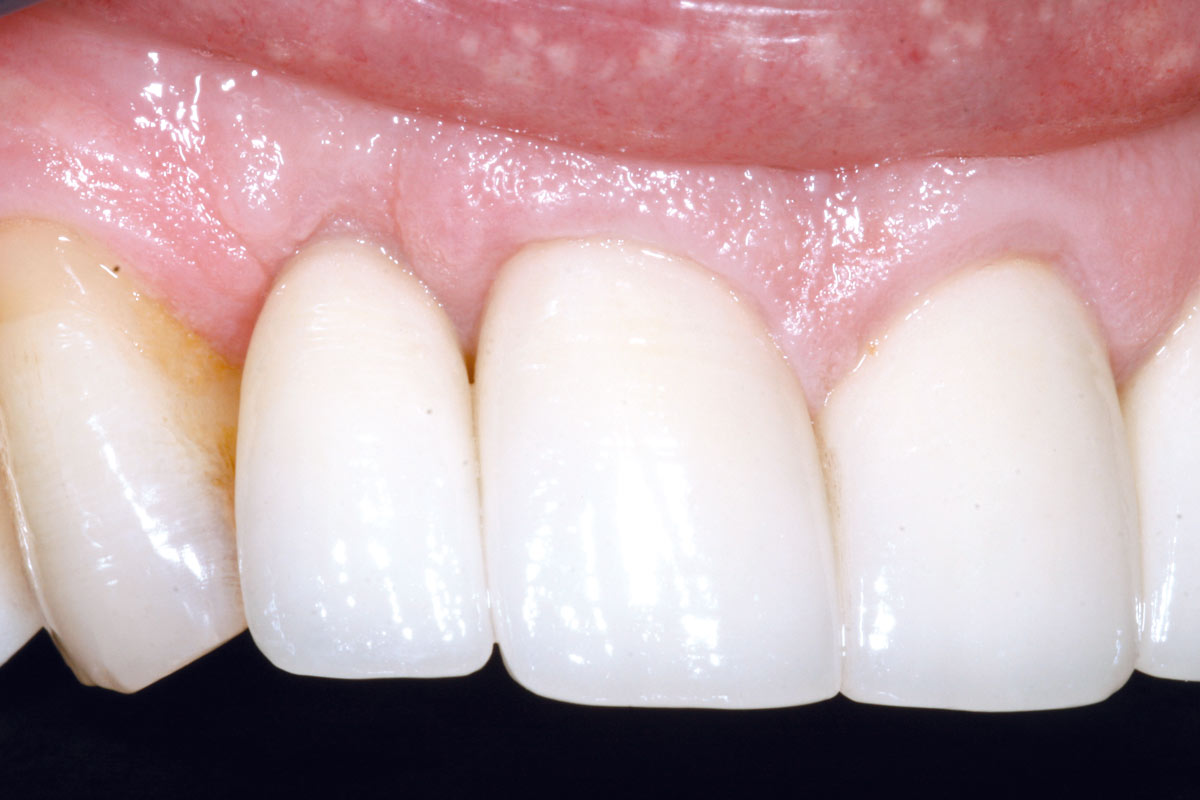

5/19 - 7 weeks after extraction of healing with a temporary tooth supported cantilever bridgeBone augementation with maxresorb® - Dr. R. Cutts

6/19 - Site without prosthetics showing sever buccal bone lossBone augementation with maxresorb® - Dr. R. Cutts